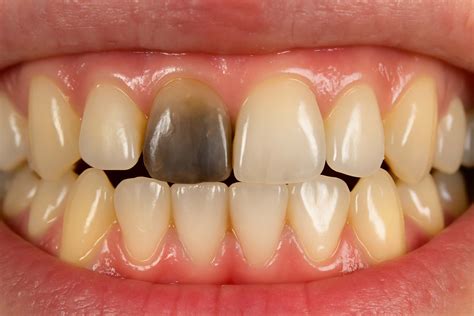

Tener un diente oscuro siempre es motivo de preocupación, aunque es una situación bastante frecuente. Puede ocurrir en niños y adultos y es una señal de que la pulpa y el nervio están sin vida. El motivo por el que un diente se oscurece es que se queda sin flujo de sangre. Por lo que su tonalidad va cambiando hasta ponerse todo negro.

Ahora, ¿qué pasa cuando un diente se pone negro? No solo se oscurece, sino que se debilita más que los demás. El cambio en la coloración no se produce de una sola vez, es paulatino y puede tomar meses o años. Esa coloración oscura es señal de que el diente está muerto; sin embargo, no siempre es posible hacer este diagnóstico a simple vista. El dolor en la pieza dental es otro indicio al que hay que estar atento. Pero las visitas al odontólogo con frecuencia son la mejor forma de detectar este problema. El especialista se encargará de hacer el diagnóstico y recomendar el tratamiento más adecuado para cada caso.

- Necrosis pulpar: Como acabamos de mencionar, la necrosis pulpar es una de las razones por las que el diente cambia de un tono blanco al negro. Significa que la pulpa, la parte blanda del diente, ha muerto y existe una infección en estos tejidos. Esto puede ocurrir a causa de un traumatismo severo ante el cual el diente no tiene capacidad de respuesta.